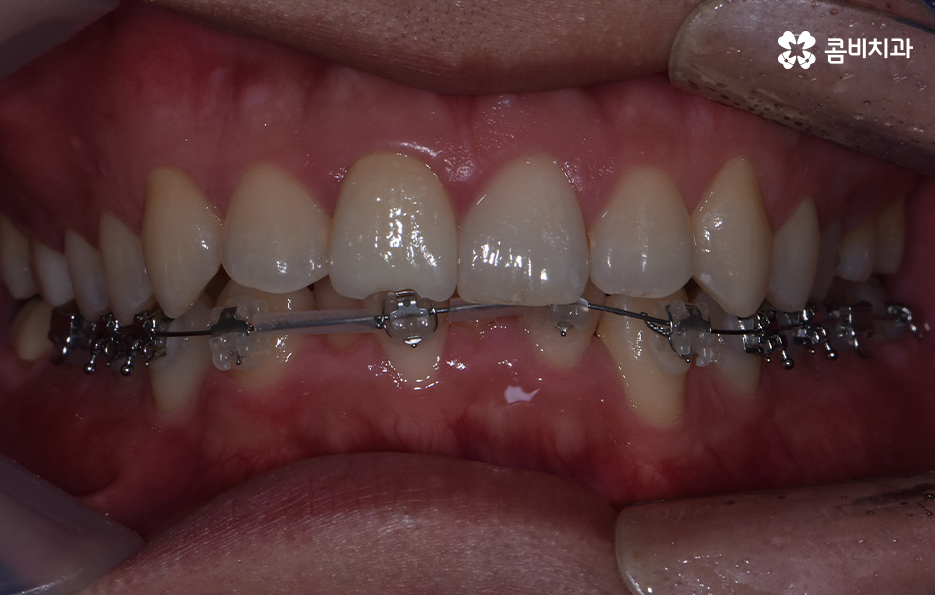

오늘은 아랫니만 교정을 한 사례를 통해서 이와 같은 고민을 하는 분들에게 도움이 될 만한 치아교정 정보를 알아보려고 하고 있어요

하지만 위에 보시는 환자분의 사례는 윗니와 아랫니의 교합을 고려하고 얼굴형, 골격 등을 고려했을 때도 아랫니만 교정이 가능했던 사례인데 일반적으로 윗니가 아랫니를 살짝 덮고 있어야 하는데 아랫니의 앞니 부분이 유독 안으로 들어와 있었기 때문에 아랫니교정 만으로도 치아교정이 가능했던 사례라고 보시면 좋을 거예요

위 환자분의 사례로 보면 아랫니 중에 하나가 유독 앞으로 튀어나와 있고 나머지 치아는 안으로 들어가 있기 때문에 교합으로 따져볼 때는 아랫니를 전체적으로 앞으로 이동시켜야 했기 때문에 비발치로도 충분히 교정이 가능했고 아랫니교정 만으로도 치료가 가능했어요